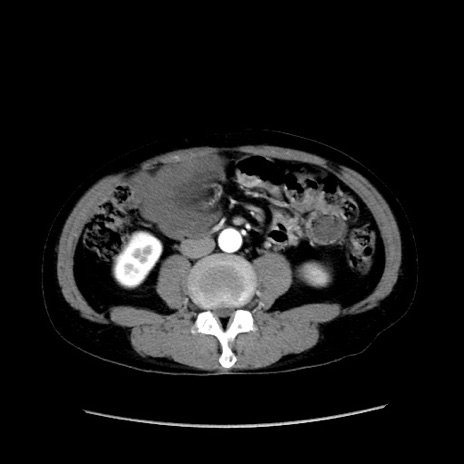

症例37(横断像)

【症例】40歳代 男性

【主訴】腹痛

【現病歴】4時間ほど前に電車に乗車中に臍部上より腹痛出現。徐々に増悪し起立困難となり、救急外来受診。生ものは数日食べていない。今朝お雑煮を食べた。

【身体所見】BT 36.8℃、BP 117/84mmHg、HR 91/min、SpO2 97%、苦悶様、腹部:臍上部広範囲圧痛あり、反跳痛±

【データ】WBC 8100、CRP 0.03